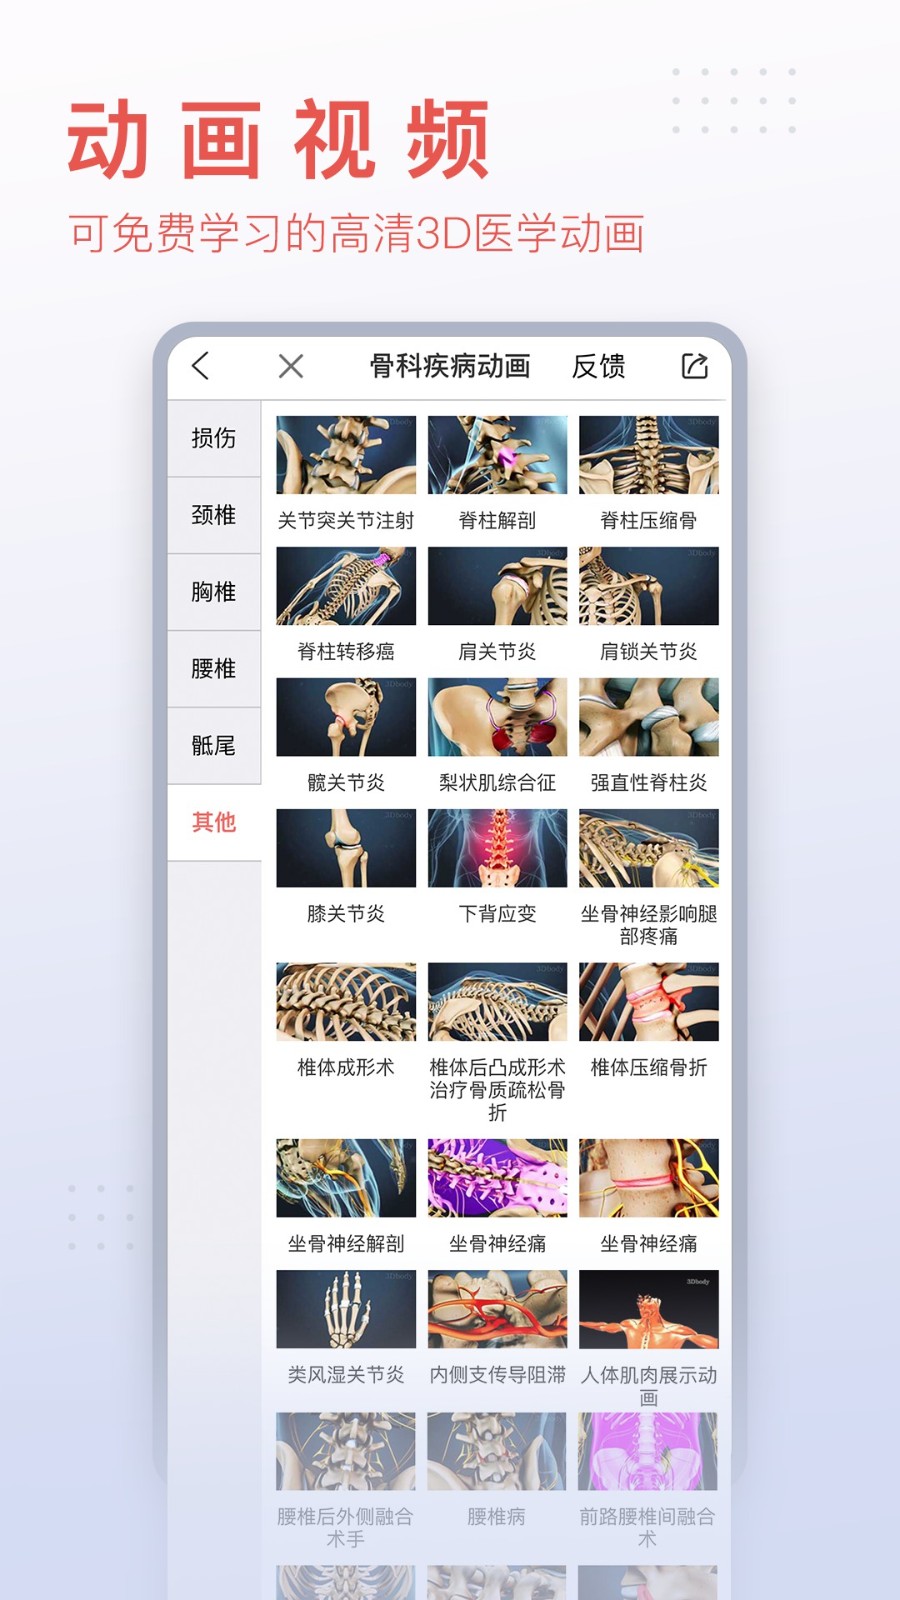

3dbody系统解剖手机版是专为医学行业打造的掌上人体解剖学习软件,详细的三维解刨图片,解释详尽。3DBody系统解剖手机版是系统模块,相较于局部模块版,解剖更加的详细,需要的赶紧下载吧。

3DBody作为集大成者,不仅数据详实,而且操作功能强大,国内外高度领先,通过本软件实时三维操作,轻易获得层层解剖人体的机会。作为内容最全面的3D解剖app,电脑版本已经被证实为最受欢迎的医学软件之一。

软件包括人体十二大系统的3D解剖.经络穴位和反射区,同时提供大量肌骨康复动画,全部三维体验,界面精美,内容专业,操作体验佳。

*骨科及医患沟通